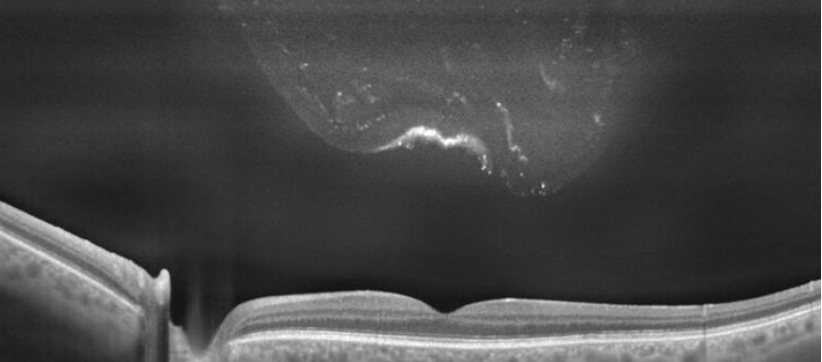

During ARVO 2021, Sunil Srivastava, MD, points out that optical coherence tomography characteristics may be predictive of the efficacy of the injections.